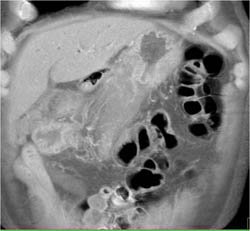

Antral Carcinoma